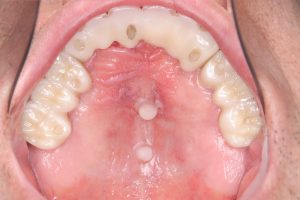

レファレンスポイントの作成は非常に重要

当クリニックでも、保険診療以外は全てデジタルスキャナー印象、全顎上下でも従来法より断然早い